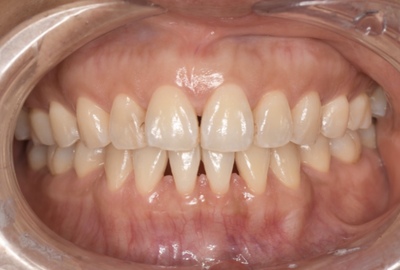

Before①

After①

| 年齢・性別 | 38歳・男性 |

| 主訴 | 下顎 歯石除去したい |

| 治療内容 | スケーリング |

| 治療期間 | 30分 |

| 治療費 | 約1,500円(保険診療) |

| リスク・副作用 | 知覚過敏、歯肉退縮 |

| 治療方針 | 歯肉縁上歯石を除去してから歯肉縁下歯石を除去します。ご自身でのプラークコントロールができるようになったら定期検診に移行します。 |

| 担当者所見 | 半年ぶりの歯科医院の受診。歯石が付きやすいためセルフケアの重要性をお伝えして、定期的にクリーニングを行います。出血率が高く炎症が強いため、今後はセルフケアを強化して歯周病治療を行います。 |